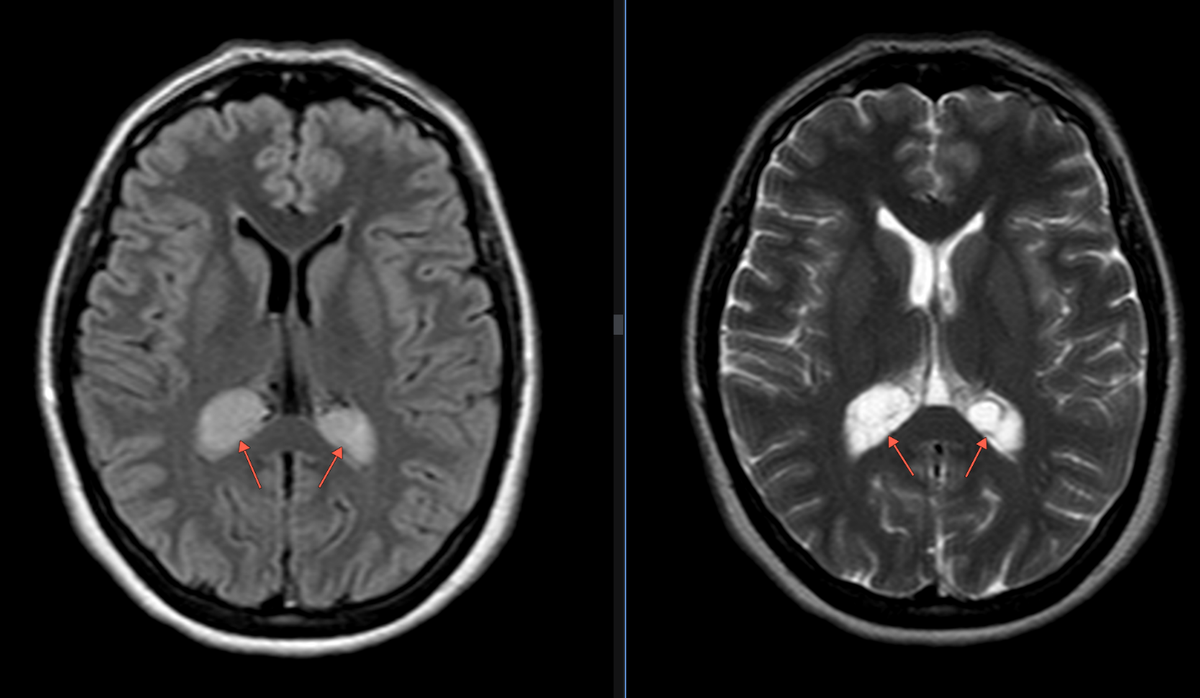

Рис.1 Пациент А.: Flair и Т2-ВИ аксиальная плоскость (слева направо): В области сосудистых сплетений задних рогов боковых желудочков с обеих сторон определяются гиперинтенсивные образования, размером справа - 1.9х2.8х2.3 см, слева - 1.8х2.1х1.9 см (двусторонние ксантогранулёмы).

Сигнальные характеристики на МРТ меняются в зависимости от смеси липидов, жидкости и продуктов крови. В целом они имитируют кистозные поражения.